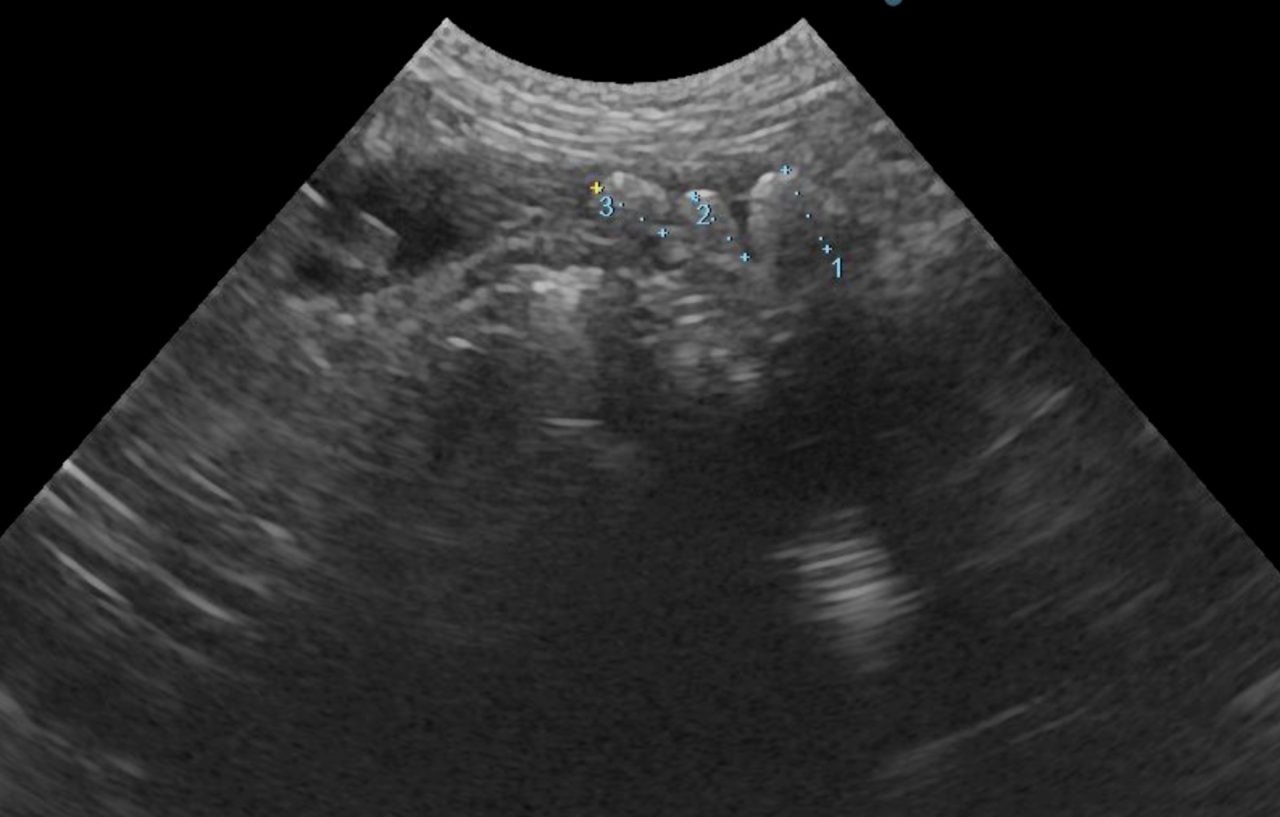

かかりつけ医で定期的に超音波検査で腎結石のモニターをしていたところ、急に腎盂が拡張してきたので早急に対応して欲しいと連絡がありました。尿管結石により尿路閉塞が起こっていました。マイクロサージェリーで尿管を2箇所切開し、尿管結石を摘除しました。術後の狭窄予防に一時的に尿管ステントを留置しています。術後翌日から、腎盂拡張は解消しましたが、術後の経過により、生体にとって異物となる尿管ステントは抜去する予定です。